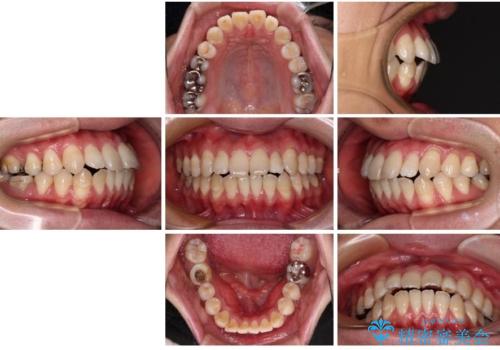

少しずつ前歯を後ろに下げていくことで、横顔のラインが整い、口元の“出っ張り感”が解消。

治療後には「自然に笑えるようになった」と嬉しいお声をいただきました。